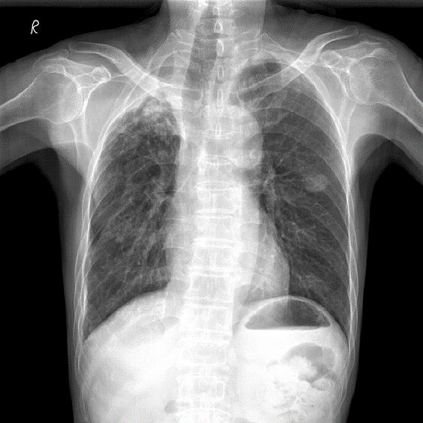

Chest X-ray (CXR) is the most typical diagnostic X-ray examination for screening various thoracic diseases. Automatically localizing lesions from CXR is promising for alleviating radiologists' reading burden. However, CXR datasets are often with massive image-level annotations and scarce lesion-level annotations, and more often, without annotations. Thus far, unifying different supervision granularities to develop thoracic disease detection algorithms has not been comprehensively addressed. In this paper, we present OXnet, the first deep omni-supervised thoracic disease detection network to our best knowledge that uses as much available supervision as possible for CXR diagnosis. We first introduce supervised learning via a one-stage detection model. Then, we inject a global classification head to the detection model and propose dual attention alignment to guide the global gradient to the local detection branch, which enables learning lesion detection from image-level annotations. We also impose intra-class compactness and inter-class separability with global prototype alignment to further enhance the global information learning. Moreover, we leverage a soft focal loss to distill the soft pseudo-labels of unlabeled data generated by a teacher model. Extensive experiments on a large-scale chest X-ray dataset show the proposed OXnet outperforms competitive methods with significant margins. Further, we investigate omni-supervision under various annotation granularities and corroborate OXnet is a promising choice to mitigate the plight of annotation shortage for medical image diagnosis.